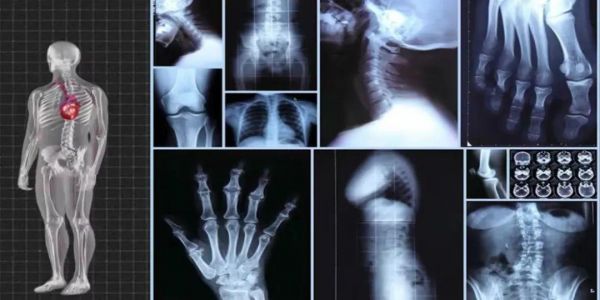

真正要警惕的是:X光和CT這對"電磁兄弟"!

想象一下:X光就像閃電俠的"超高速快照",用極短波長給骨骼拍特寫。

而CT更像廚神的"切片神器",360度掃描把身體切成千層蛋糕。